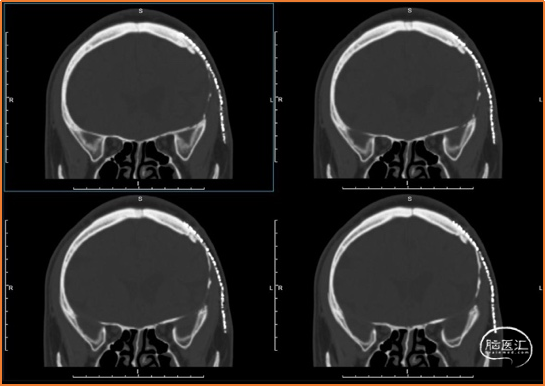

术前检查

术前诊断

1. 脑外伤后遗症,癫痫。

2. 颅骨修补材料凹陷。